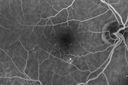

70 year old man with diabetes. OCT scan showed edema vision is 20/25 and the patient is not bothered. The edema did not progress